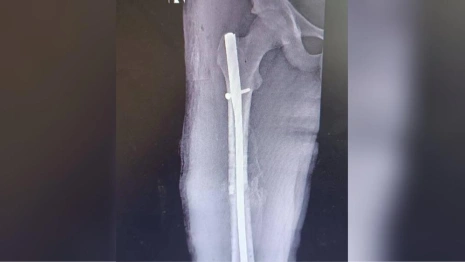

Медики применили инновационный метод лечения – блокирующий интрамедуллярный остеосинтез. Операция прошла успешно, без разрезов и с минимальным риском осложнений.